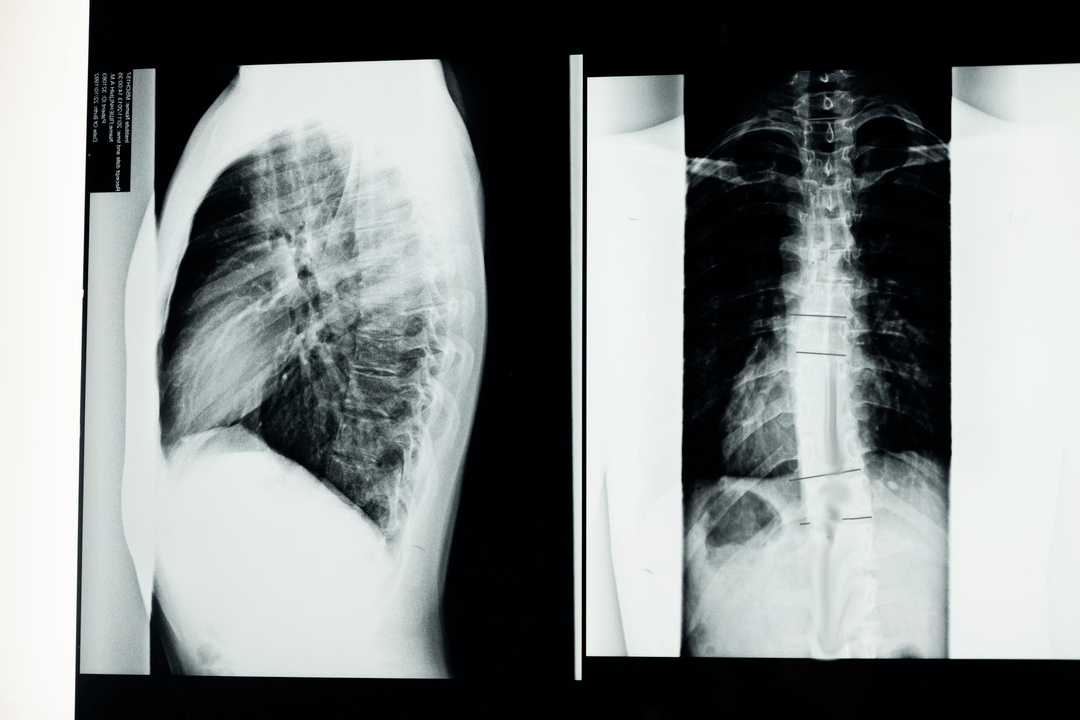

Before starting diagnostic tests, the neurologist collects the patient's medical history and carefully studies his complaints.Osteochondrosis has common symptoms with some other diseases, so it is important to be able to distinguish pathologies.X-ray examinations will help to confirm the diagnosis of osteochondrosis: radiography, myelography and computed tomography.

An exploratory X-ray allows you to get an X-ray image of the spine or part of it.In this way, the doctor can determine the place affected by the disease.For greater clarity, we will explain how osteochondrosis can be determined by an X-ray: the image will show a narrowing of the intervertebral disc, the presence of bone growths (osteophytes) or a change in the shape of the spinal segment.